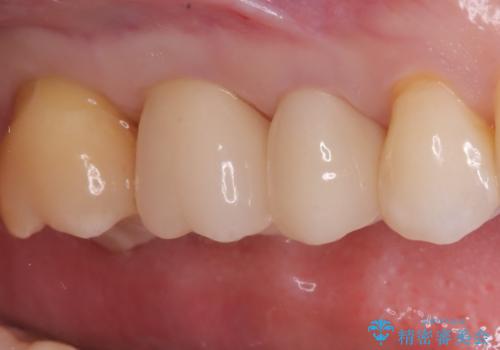

虫歯治療後は、形やかみ合わせを細かく調整しながら、セラミッククラウンを作製・装着しました。金属を使わないセラミックは見た目が自然なだけでなく、適合性も高いため、再びむし歯になるリスクを抑えることができます。

治療後は、見た目の改善だけでなく、咬み心地や違和感の改善にもつながり、患者さんからは「しっかり噛めるようになって安心した」との声をいただきました。